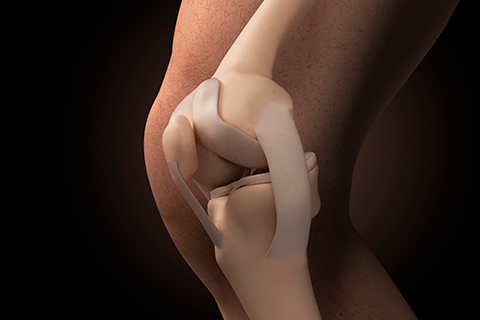

• 십자인대파열

무릎 관절의 안정성을 유지시켜 주는 십자인대가 파열된 질환입니다.

십자인대파열 치료방법

• 비수술적 치료 약물치료, 보조기 착용

• 수술적 치료 전장십자인대 재건술

• 반월상연골판파열

반월상 연골판 파열은 가장 흔한 무릎 부상 중 하나로 신체접촉이 많은 운동선수들에게 발생할 위험이 높은 질환입니다.

반월상연골판파열 치료방법

• 비수술적 치료 약물치료, 물리치료, 주사치료

• 수술적 치료 반월상 연골 절제술, 반월상 연골 봉합술, 반월상 연골 이식술

• 무릎연골손상

무릎연골손상은 퇴행성관절염을 앞당기는 질환으로 퇴행성이나 외상에 의해 손상되어 발생합니다.

무릎연골손상 치료방법

• 수술적 치료 자가연골 이식술, 줄기세포 이식술, 미세천공술, 아티필름, 연골세포 배양이식술